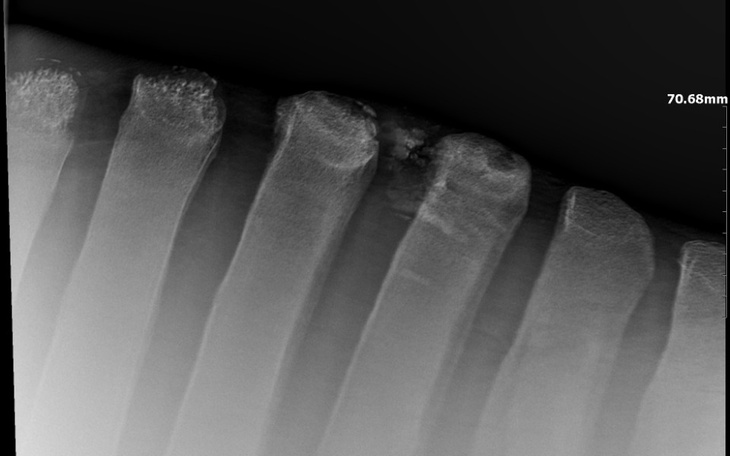

zdecydowałam się skonsultować konia z innym weterynarzem. Tym razem zdęcie RTG pokazało prawdziwą przyczynę problemów- odłamki wyrostków kostnych, które są przyczyną chronicznego stanu zapalanego w kłębie. Usunąć można je wyłącznie operacyjnie.